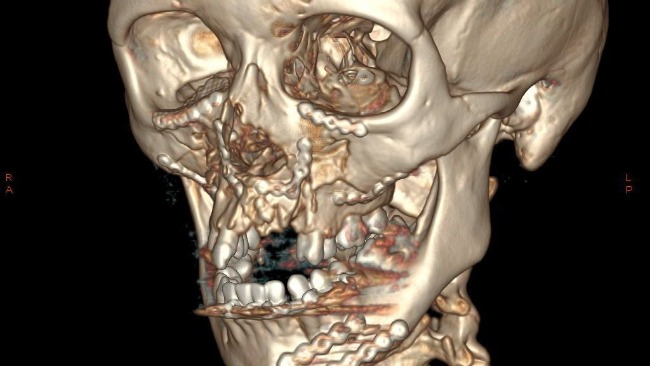

Я получил серьезные травмы:

полностью сломаны лицевые кости,

выбиты все верхние зубы и некоторые нижние,

сломаны кости под глазами, сломан затылок,